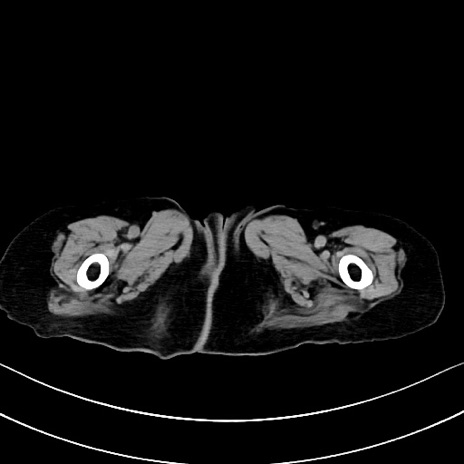

症例40(横断像)他院1日前

横断像

他院CT